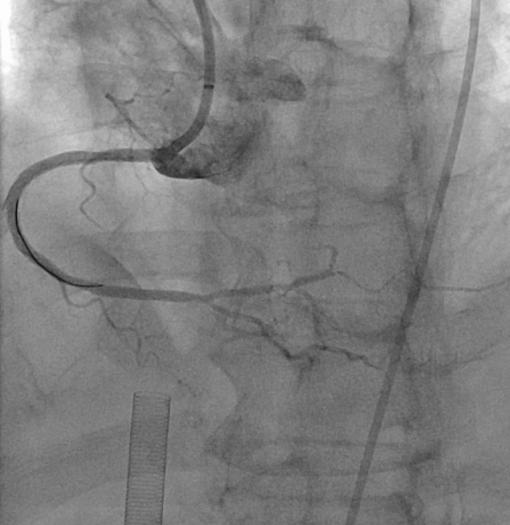

麻醉顺利,血管外科通道建立,ECMO成功运转,但困难如期而至。患者的左右血管都存在严重病变,其中右边是完全闭塞的,而且看不出堵塞的入口在哪里,进攻的导丝没有方向,这类病变处理的难度系数是最高的。罗裕主任凭借丰富的手术经验,利用不同导丝的触觉反馈,首先将微导管引导入冠脉结构,再换用不同硬度和不同塑形的导丝成功突破远端纤维帽,有惊无险的开通了右边血管。

左图术前右冠,右图术后右冠